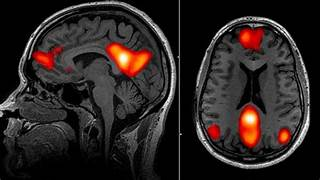

Neurociencias